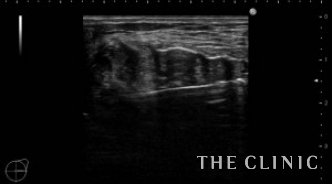

6㎝のしこりの被膜は肥厚し、内部は充実性のしこり(脂肪壊死)とオイルの両方を認めます。肥厚した被膜を破りチューメセント(麻酔)を注入して、脂肪壊死を崩すためベイザーリポを使用します。

脂肪が崩れた後は吸引を行い、しこりは消失しました。右側は吸引除去した壊死脂肪です。